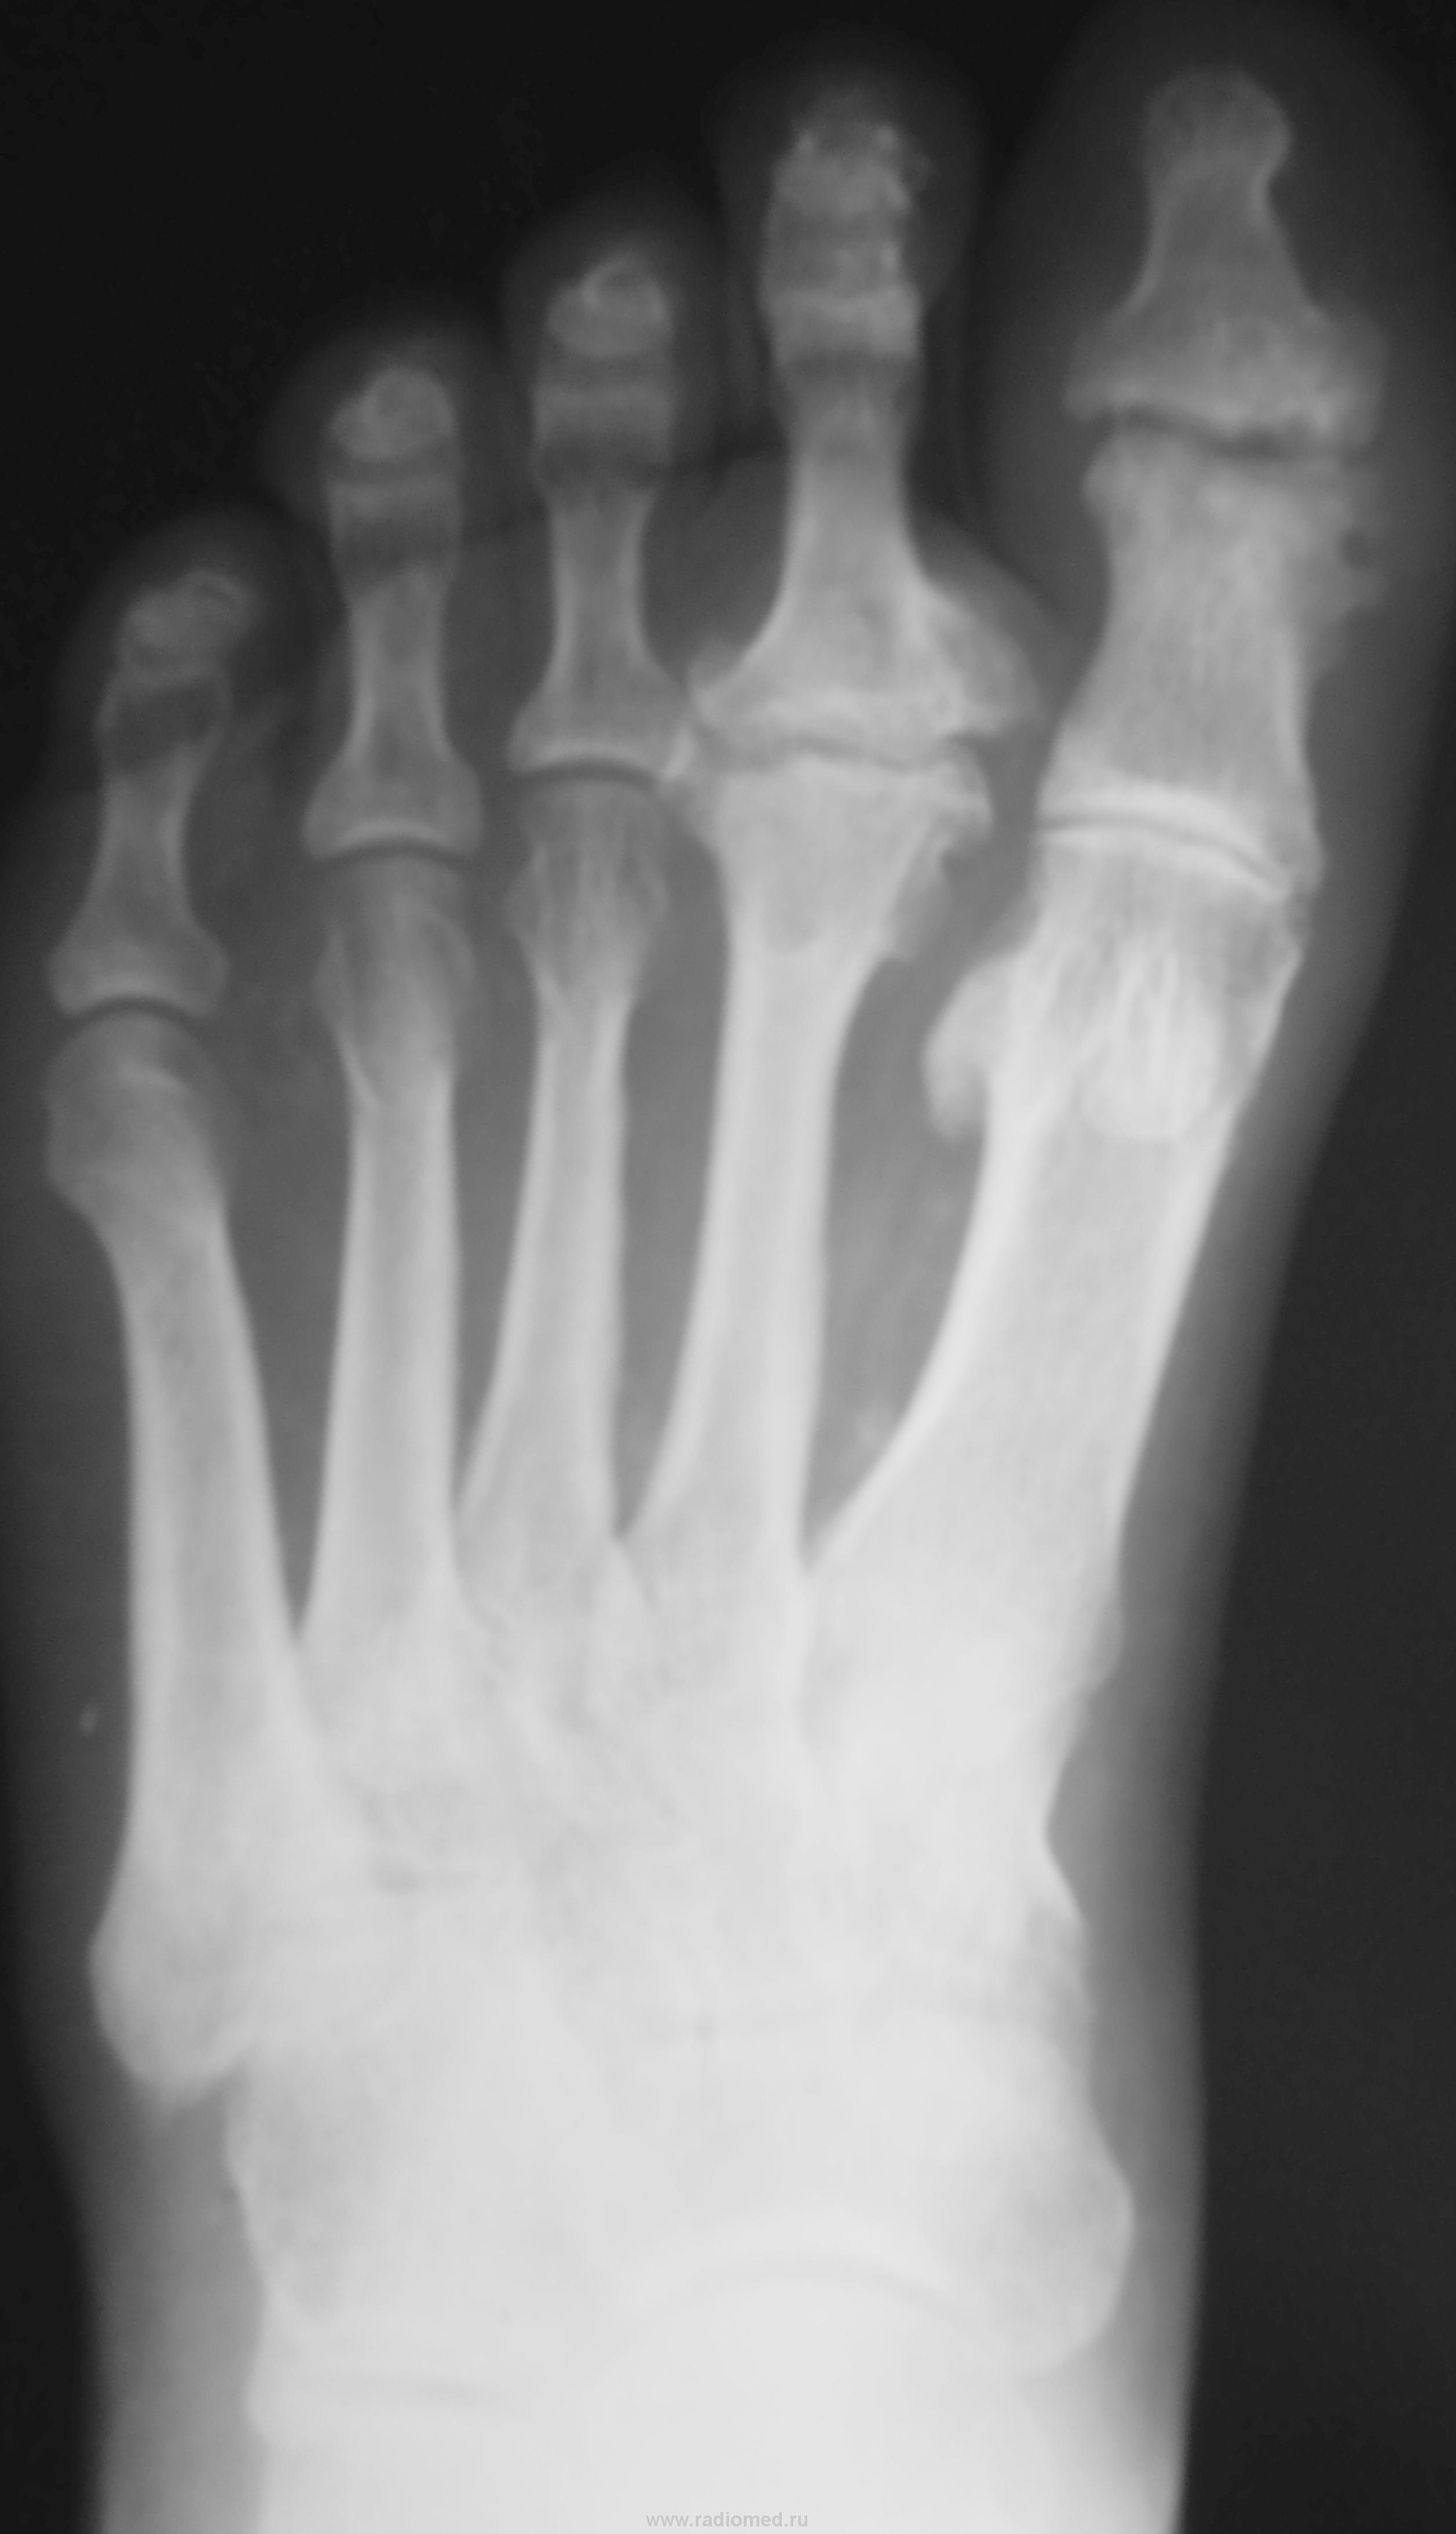

Подагра. Болезнь А. Келера II.

Келлера2, действительно. Но думаю, что 1 палец похож на остеомиелитный, тем более, что хорошо видны частично склерозированные сосуды. Что у пациетна с сахарами?

Келлер2. Остеомиелит или посттравматические изменения. Для подагры слишком круглый и без склероза.

А поражения так же и ногтевой фаланги второго пальца нет?

Пробойники при подагре как раз круглые

Тогда гда медиальная стенка тофуса и ободок склероза?

По мне - остеофиты это все.